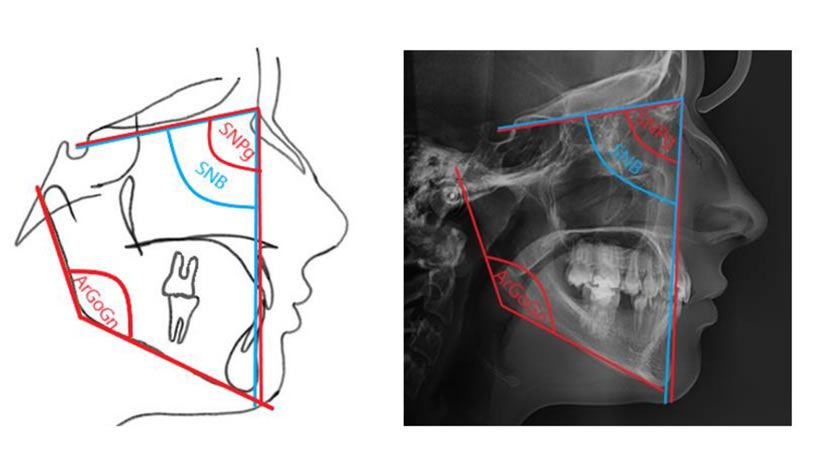

Asociación de patrones craneofaciales con la curva de Spee

y el tiempo necesario para la nivelación de ortodoncia